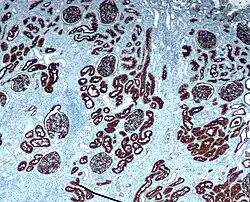

Neprilysin is expressed in a wide variety of tissues and is particularly abundant in kidney. It is also a common acute lymphocytic leukemia antigen that is an important cell surface marker in the diagnosis of human acute lymphocytic leukemia (ALL). This protein is present on leukemic cells of pre-B phenotype, which represent 85% of cases of ALL.[5]

Hematopoietic progenitors expressing CD10 are considered "common lymphoid progenitors", which means they can differentiate into T, B or natural killer cells.[6] CD10 is of use in hematological diagnosis since it is expressed by early B, pro-B and pre-B lymphocytes, and by lymph node germinal centers.[7] Hematologic diseases in which it is positive include ALL, angioimmunoblastic T cell lymphoma, Burkitt lymphoma, chronic myelogenous leukemia in blast crisis (90%), diffuse large B-cell lymphoma (variable), follicular center cells (70%), hairy cell leukemia (10%), and myeloma (some). It tends to be negative in acute myeloid leukemia, chronic lymphocytic leukemia, mantle cell lymphoma, and marginal zone lymphoma. CD10 is found on non-T ALL cells, which derive from pre-B lymphocytes, and in germinal center-related non-Hodgkin lymphoma such as Burkitt lymphoma and follicular lymphoma, but not on leukemia cells or lymphomas, which originate in more mature B cells.[8]

CD10 is used in clinical pathology for diagnostic purpose.

In lymphomas and leukemias

- Acute lymphoblastic leukemia (ALL) cells are CD10+.

- Follicular lymphoma (follicle centre cell lymphoma) are CD10+.

- Burkitt Lymphoma cells are CD10+.

- CD10+ diffuse large B cell lymphoma (CD10+ DLBCL)[20]

- Angioimmunoblastic T cell lymphoma (AITL) are CD10+[25][26] and distinguishes AITL from other T cell lymphomas (CD10−)[27]

- Some benign T cells can be CD10+[28]

In epithelial tumors

- Clear cell renal cell carcinoma (Clear cell RCC)

- CD10+ distinguishes renal cell carcinoma, conventional type with eosinophilic morphology from its mimickers. Chromophobe carcinoma and oncocytoma are CD10−.[29]